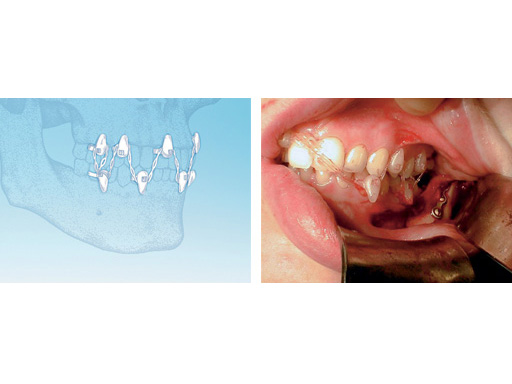

The Rapid IMF System has been developed in response to this request. This device is an innovative, adjustable flexible band, which is wrapped around individual teeth, similar to an orthodontic band. A long elastic chain is then looped around the strategically placed brackets to achieve IMF.

To apply the Rapid IMF, at least six, preferably eight points are chosen for the placement of the nylon anchorage ties. After tightening and excess removal of all belts, a link of the elastic chain is passed over an anterior anchorage point and is looped over all anchorage ties in a zigzag manner and secured over an easily accessible upper anterior anchorage point.